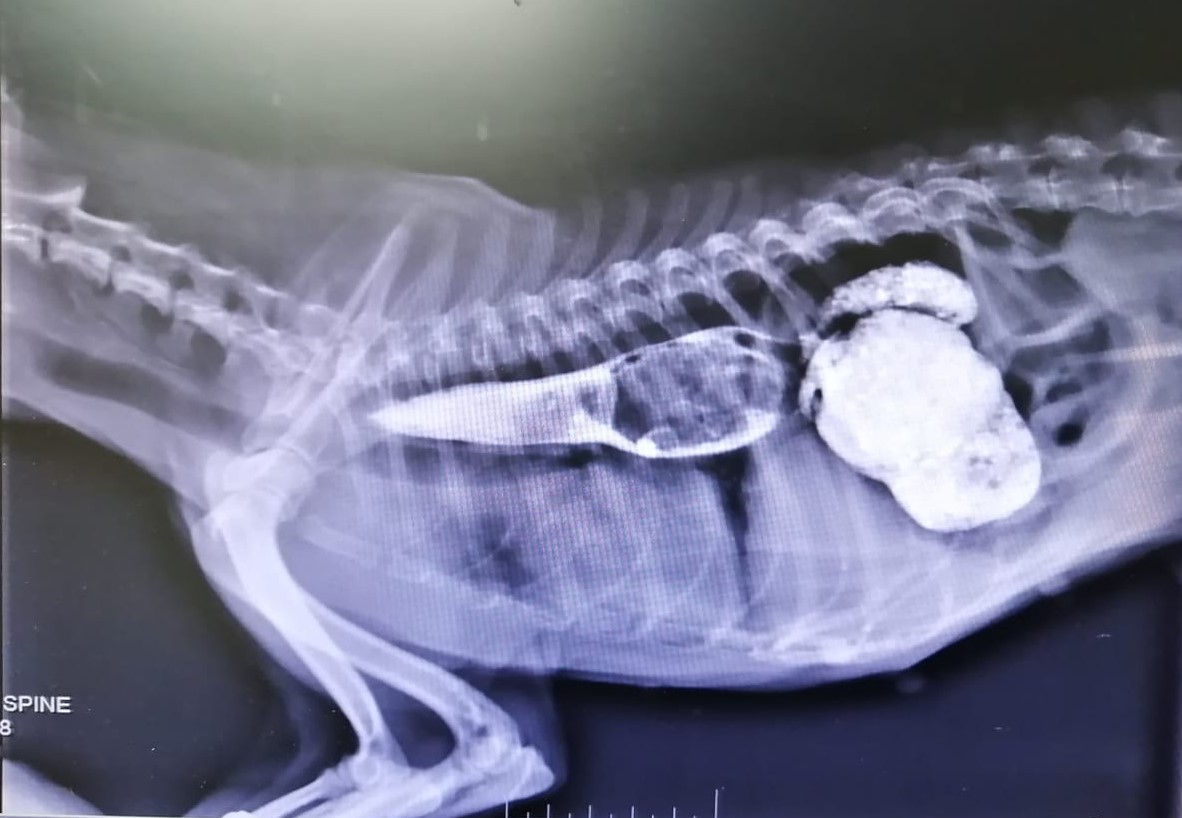

Aangesien die simptome gewoonlik vaag is, kan hierdie 'n moelike diagnose wees. Indien dit enigsins vermoed word, word X-straalfoto's van die borskas geneem. Is daar geen duidelike tekens op die foto nie, word kontrasmiddel per mond gegee en opvolgfoto's geneem. Dikwels word die letsels dan duidelik in die slukderm tussen die hart en diafragma gesien. (Sien Fig. 2)

Barium wys wit op op X-straalfoto's. In die foto hierbo kan duidelik gesien word hoe 'n gedeelte van die Bariummaal aan die linkerkant van die Spirocercaletsel vassteek. Die letsel self wys as 'n donker kol met klein strepies wit daaromheen net skuins bo die hart. 'n Gedeelte van die Bariummaal het deurgegaan na die maag aan die regterkant.